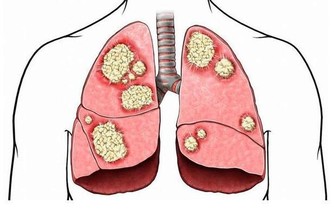

長時間的大量抽煙容易給血管添堵,抽煙本身就是不好的行為,在煙草中有害物質攝入過量時容易加速血管的粥樣硬化,甚至攝入過多的尼古丁,焦油等物質而對血管健康受損造成影響,久而久之血管病變的概率會增加。為了防止血管堵塞,出現老化,硬化的情況,平時應該遠離煙草,養成健康良好的習慣。